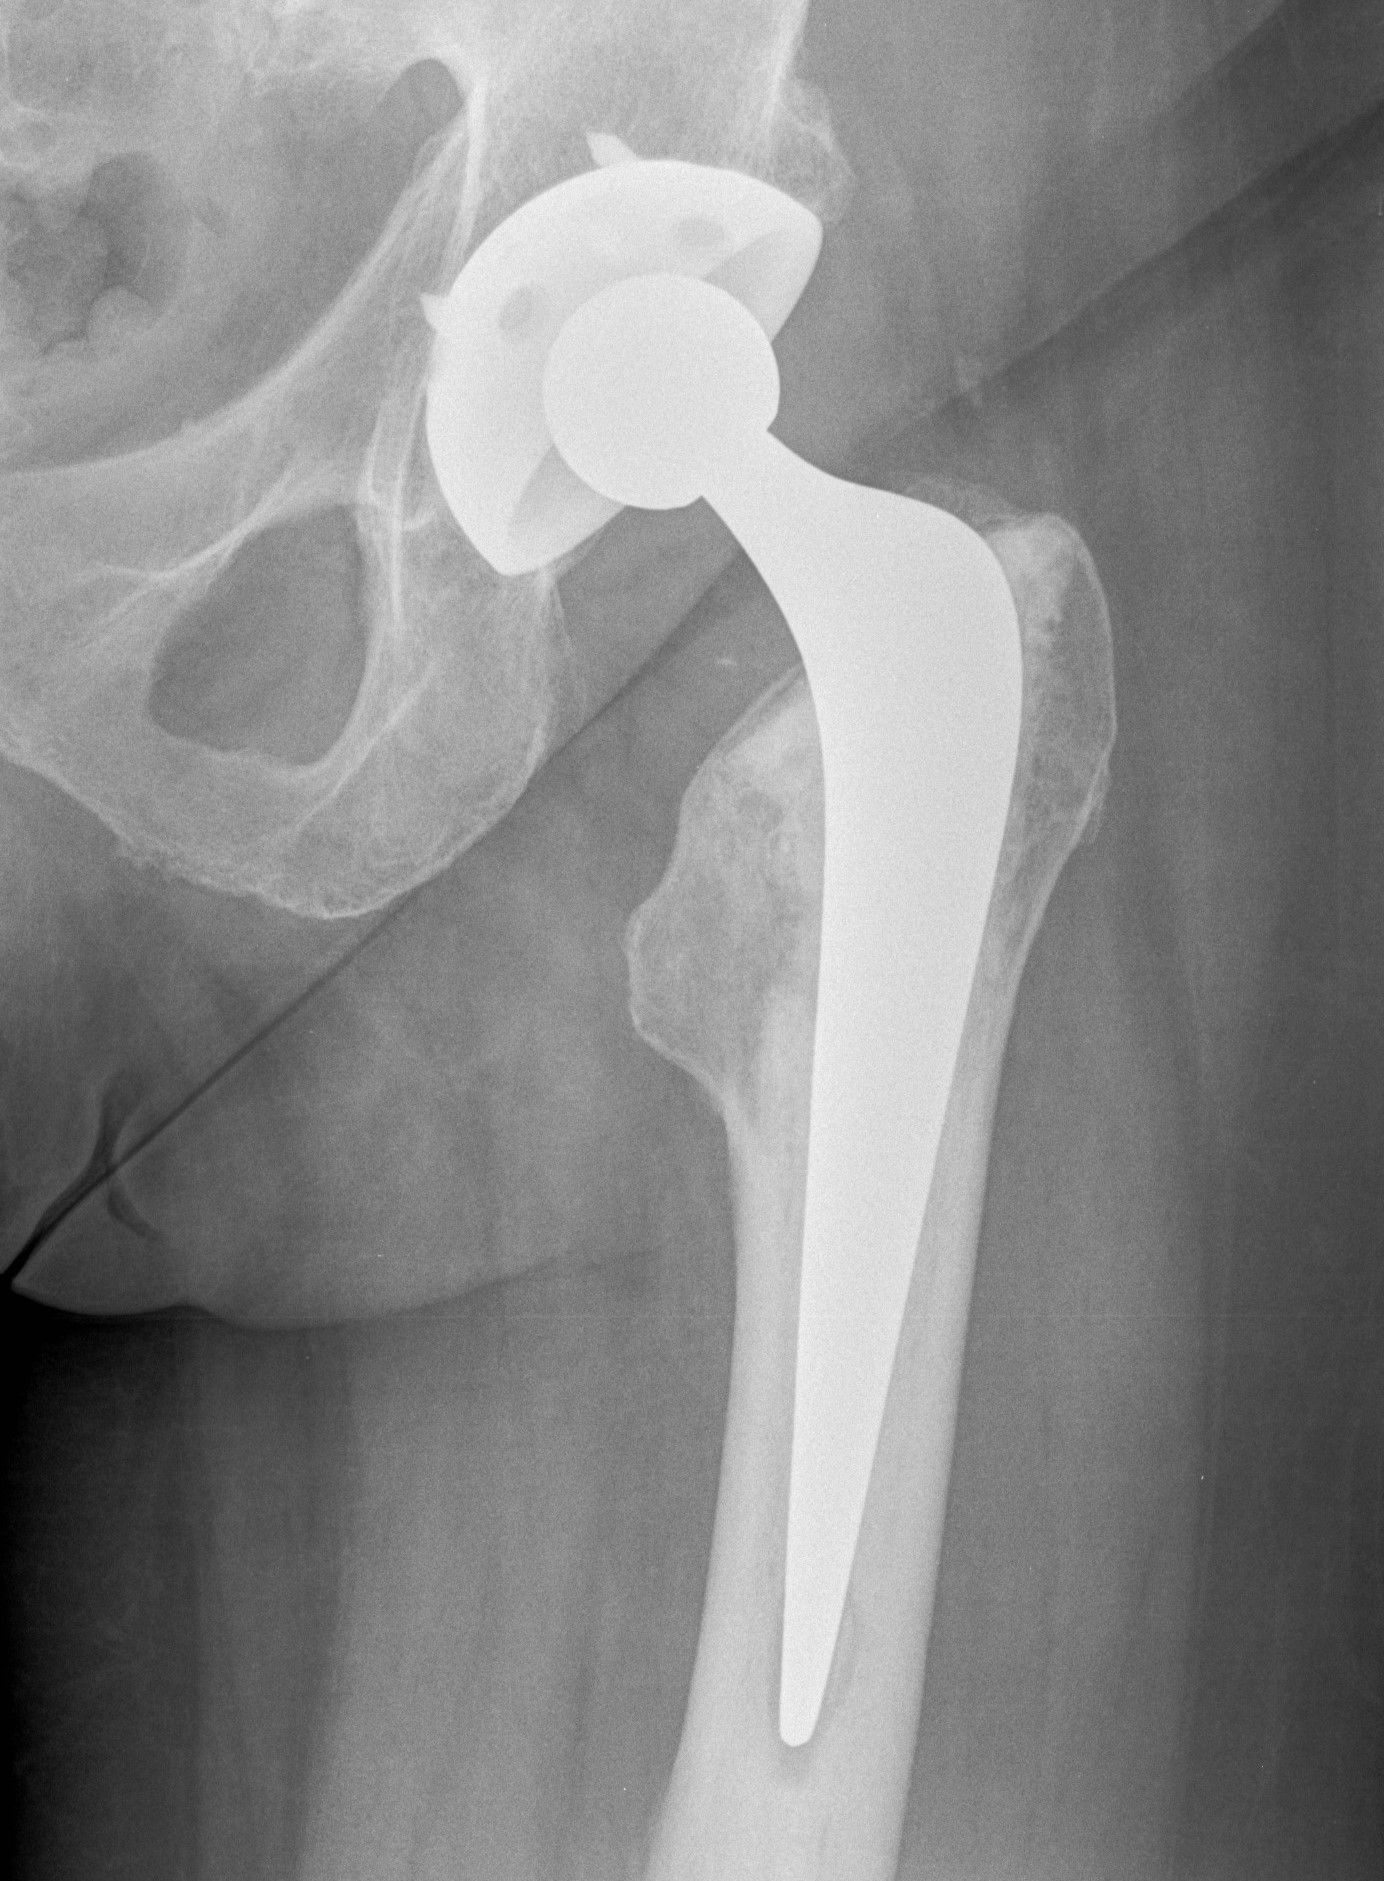

Below are the prostheses with links we commonly use but this is not exhaustive.